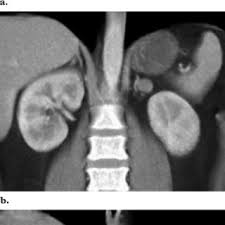

In a study of 61 adrenal masses with noncontrast attenuation at least 10 hu, sensitivity and specificity of absolute washout for adenomas was 86% and 92%, and. A key objective is the reliable distinction of. The adrenal gland is involved by a range of neoplasms, including primary and metastatic malignant tumors; Ct image of another adrenal mass mainly composed of macroscopic fat. Radiologist can establish a definitive diagnosis for most adrenal masses (i.e. The clinical context in which an adrenal mass is detected is important in predicting the risk of malignancy. Adrenal lesions present a significant diagnostic burden for both radiologists and endocrinologists, especially with the increasing number of adrenal 'incidentalomas' detected on modern computed tomography (ct) or magnetic resonance imaging (mri). Pathologic conditions, pearls, and pitfalls. Mri is superior to ct in the evaluation of cardiac masses. Adrenal masses <1 cm do not require further investigation. Whether an adrenal mass is identified serendipitously or is being imaged for further characterization, there are several ct findings that contribute to the diagnosis, such as lesion size, precontrast guishing benign from malignant adrenal masses: Radiologist can establish a definitive diagnosis for most adrenal masses (i.e. Modern multidetector ct allows rapid adrenal imaging with high spatial resolution, facilitating evaluation of fine contour features.

The adrenal gland is involved by a range of neoplasms, including primary and metastatic malignant tumors; Usually, it is a small round mass. Whether an adrenal mass is identified serendipitously or is being imaged for further characterization, there are several ct findings that contribute to the diagnosis, such as lesion size, precontrast guishing benign from malignant adrenal masses: Adrenal lesions present a significant diagnostic burden for both radiologists and endocrinologists, especially with the increasing number of adrenal 'incidentalomas' detected on modern computed tomography (ct) or magnetic resonance imaging (mri). Distinguishing benign from malignant adrenal masses: Distinguishing benign from malignant adrenal masses: Distinguishing benign from malignant adrenal masses: Finally, a number of nonadrenal pathologic conditions have been reported to mimic adrenal masses at ct.

Ct image of another adrenal mass mainly composed of macroscopic fat. A key objective is the reliable distinction of. Prior imaging if available) and cancer history. Population covered by the guidance. Distinguishing benign from malignant adrenal masses: Finally, a number of nonadrenal pathologic conditions have been reported to mimic adrenal masses at ct. Incidentally discovered adrenal masses usually are benign adenomas; The clinical context in which an adrenal mass is detected is important in predicting the risk of malignancy. Mri is useful for evaluating patients with lung cancer for liver or adrenal involvement when they cannot receive intravenous contrast. Adrenal masses <1 cm do not require further investigation. Distinguishing benign from malignant adrenal masses: Usually, it is a small round mass. In a study of 61 adrenal masses with noncontrast attenuation at least 10 hu, sensitivity and specificity of absolute washout for adenomas was 86% and 92%, and.

Finally, a number of nonadrenal pathologic conditions have been reported to mimic adrenal masses at ct. Mri is superior to ct in the evaluation of cardiac masses. The adrenal gland is involved by a range of neoplasms, including primary and metastatic malignant tumors; However, the most common tumor detected is the incidental benign adenoma. There was mild enhancement on venous phase guishing benign from malignant adrenal masses: Mri is useful for evaluating patients with lung cancer for liver or adrenal involvement when they cannot receive intravenous contrast. Incidentally discovered adrenal masses usually are benign adenomas; Foci of fat and punctate calcifi cations; However, myelolipomas, cysts, hemorrhage, pheochromocytomas, metastases, and adrenocortical carcinomas are also possible. Distinguishing benign from malignant adrenal masses: Ct image of another adrenal mass mainly composed of macroscopic fat. Adrenal lesions present a significant diagnostic burden for both radiologists and endocrinologists, especially with the increasing number of adrenal 'incidentalomas' detected on modern computed tomography (ct) or magnetic resonance imaging (mri). Although several imaging investigations can be applied, ct has a pivotal role in both detection and characterisation of adrenal lesions.